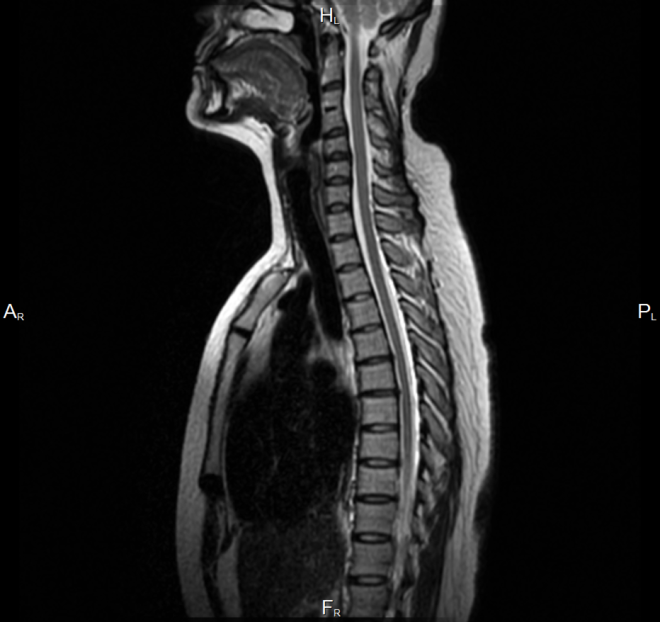

В современной медицине для исследования позвоночного столба в области груди приоритетным методом обследования является МРТ грудного отдела позвоночника. Принцип работы магнитно-резонансной томографии заключается в получении объемных изображений тканей в различных проекциях. Благодаря таким снимкам специалисты имеют возможность детально рассмотреть структуры позвоночника с любой стороны и под любым углом, изучить все анатомические особенности строения позвоночного столба, увидеть патологии спинного мозга, определить форму и стадию дегенеративных изменений в межпозвоночных дисках, а также заранее смоделировать ход планируемого хирургического лечения. Такая сверхточность и информативность диагностики достигается неинвазивным способом - без малейшего вмешательства в организм пациента и без причинения ему болезненных и неприятных ощущений. За счет полного отсутствия облучения на человека метод МРТ позвоночника считается безопасным и применяется детям, беременным и кормящим женщинам, онко

МРТ грудного отдела позволяет оценивать все структуры данной области – позвонки, связки и суставы, межпозвоночные диски, хрящи, мышцы, мягкие ткани, спинной мозг и его оболочки, состояние позвоночного канала.  Единственное, что не очень хорошо визуализирует МРТ, - это качество костей, и для диагностики костных патологий пациента обычно направляют на КТ грудного отдела позвоночника.

Магнитно-резонансная томография грудного отдела безошибочно поможет в выявлении следующих состояний и заболеваний:

• врожденные аномалии развития позвоночника и спинного мозга;

• сужения, деформации позвоночного канала;

• межпозвоночные грыжи, протрузии;

• травматические повреждения позвоночника и спинного мозга;

• воспалительные заболевания тканей позвоночной системы;

• остеохондроз;

• артрит и артроз;

• дистрофические изменения в позвонках и дисках;

• дегенеративные заболевания центральной нервной системы – рассеянный склероз;

• доброкачественные и злокачественные новообразования и метастазы;

• сосудистые патологии и нарушения кровообращения тканей обследуемой области.